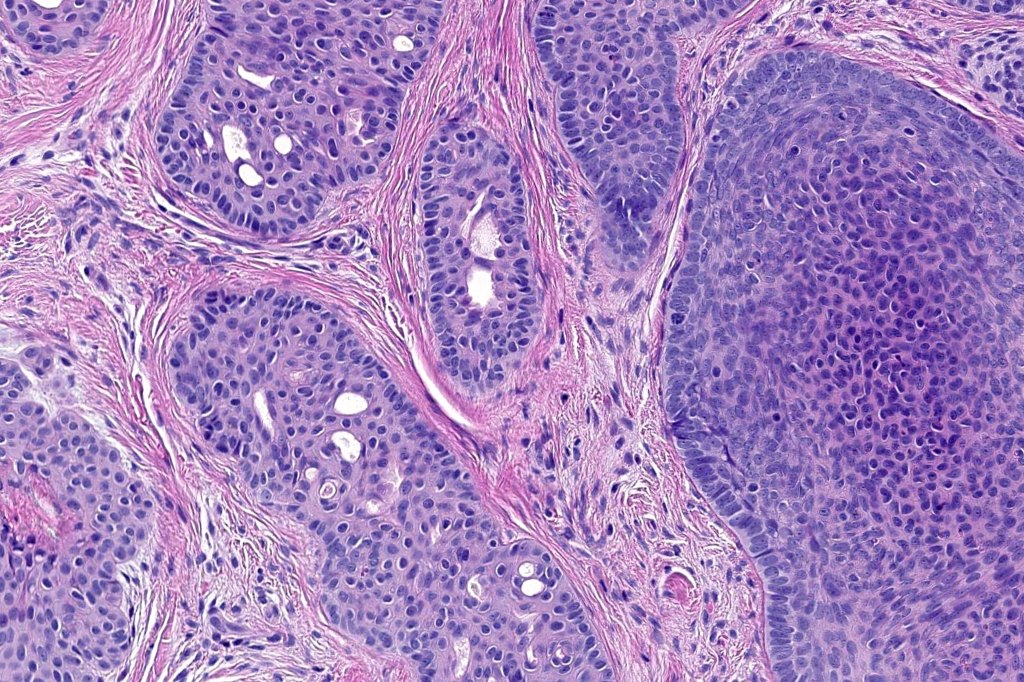

Histological features

•Biphasic tumors comprising germinative epithelial and mesenchymal components

•Sharply circumscribed nodule, sometimes with a pseudocapsule

•Uniform basaloid cells with peripheral palisading and often marked mitotic activity

•No pleomorphism

•Absence of retraction artifact and mucin deposition

•Variable keratin cysts

•Cribriform and palisaded (rippled) pattern

•Stromal amyloid often present